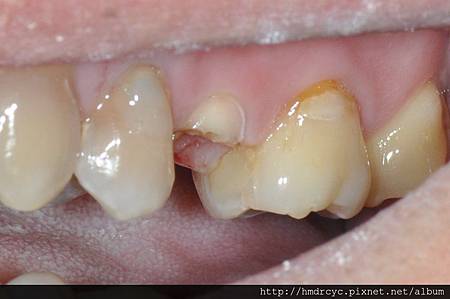

牙齒因為外傷斷裂或嚴重蛀牙

有可能整個牙冠都損失掉

牙肉上牙冠部分就算完全缺損了

橋頭的K小姐有相同問題門牙斷裂

經過X光評估建議先裝鑄心恢復

高雄欣美牙醫先幫忙把根管治療完成

裝上鑄心後牙齒的高度寬度都恢復